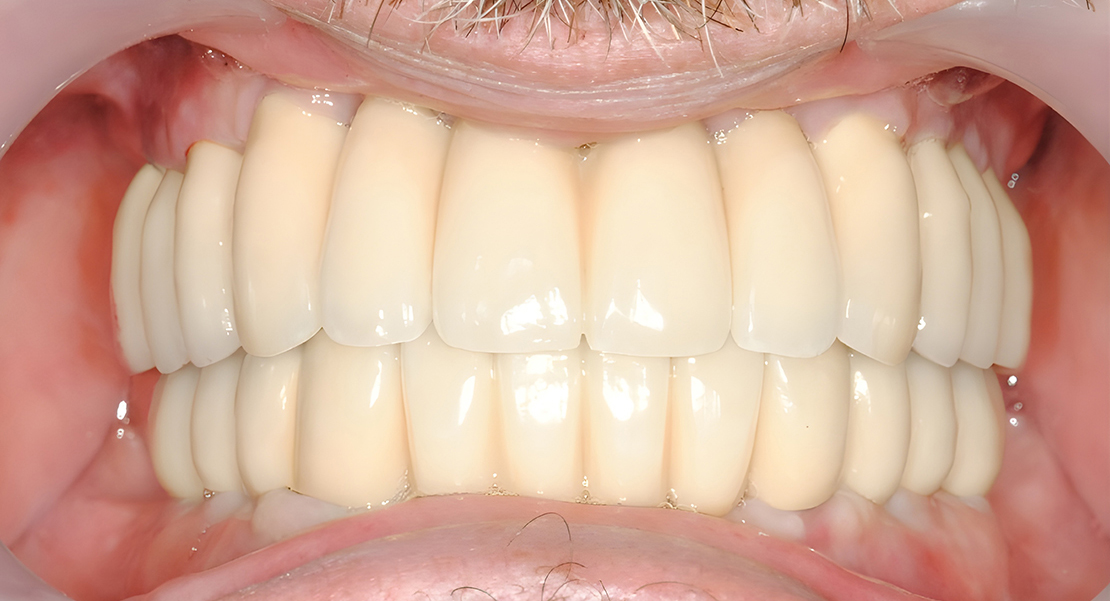

If you are suffering from a wide range of mouth or dental issues, or one specific issue that threatens to cause more issues to arise in the future, you may need to consider a full mouth rehabilitation.

The plan for full mouth rehabilitation may include a combination of treatments, such as implants, crowns, gum treatment, other restorative procedures, and in some cases orthodontic treatment.

Based on the assessment results from a comprehensive examination, our dental specialist will create a customized treatment plan to address your specific dental needs.

Restorations

Completed